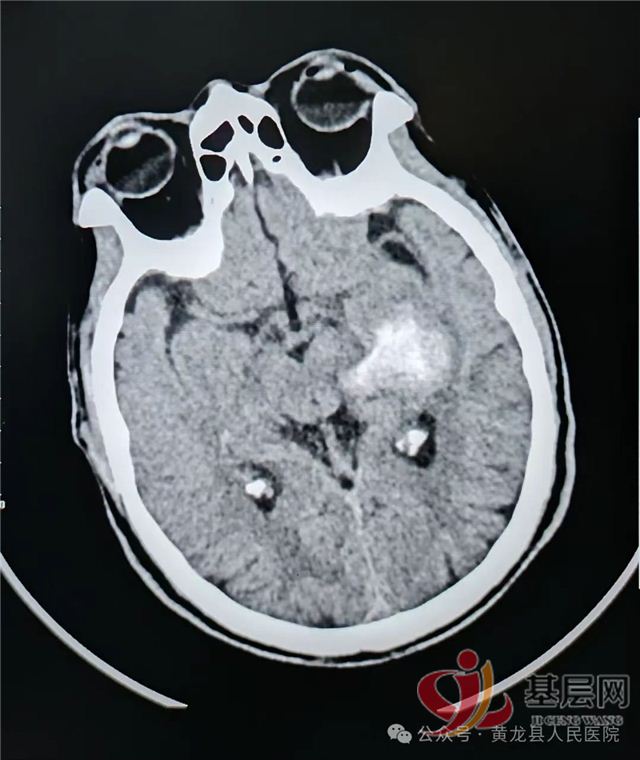

左侧内囊--丘脑区脑出血(约11ml)